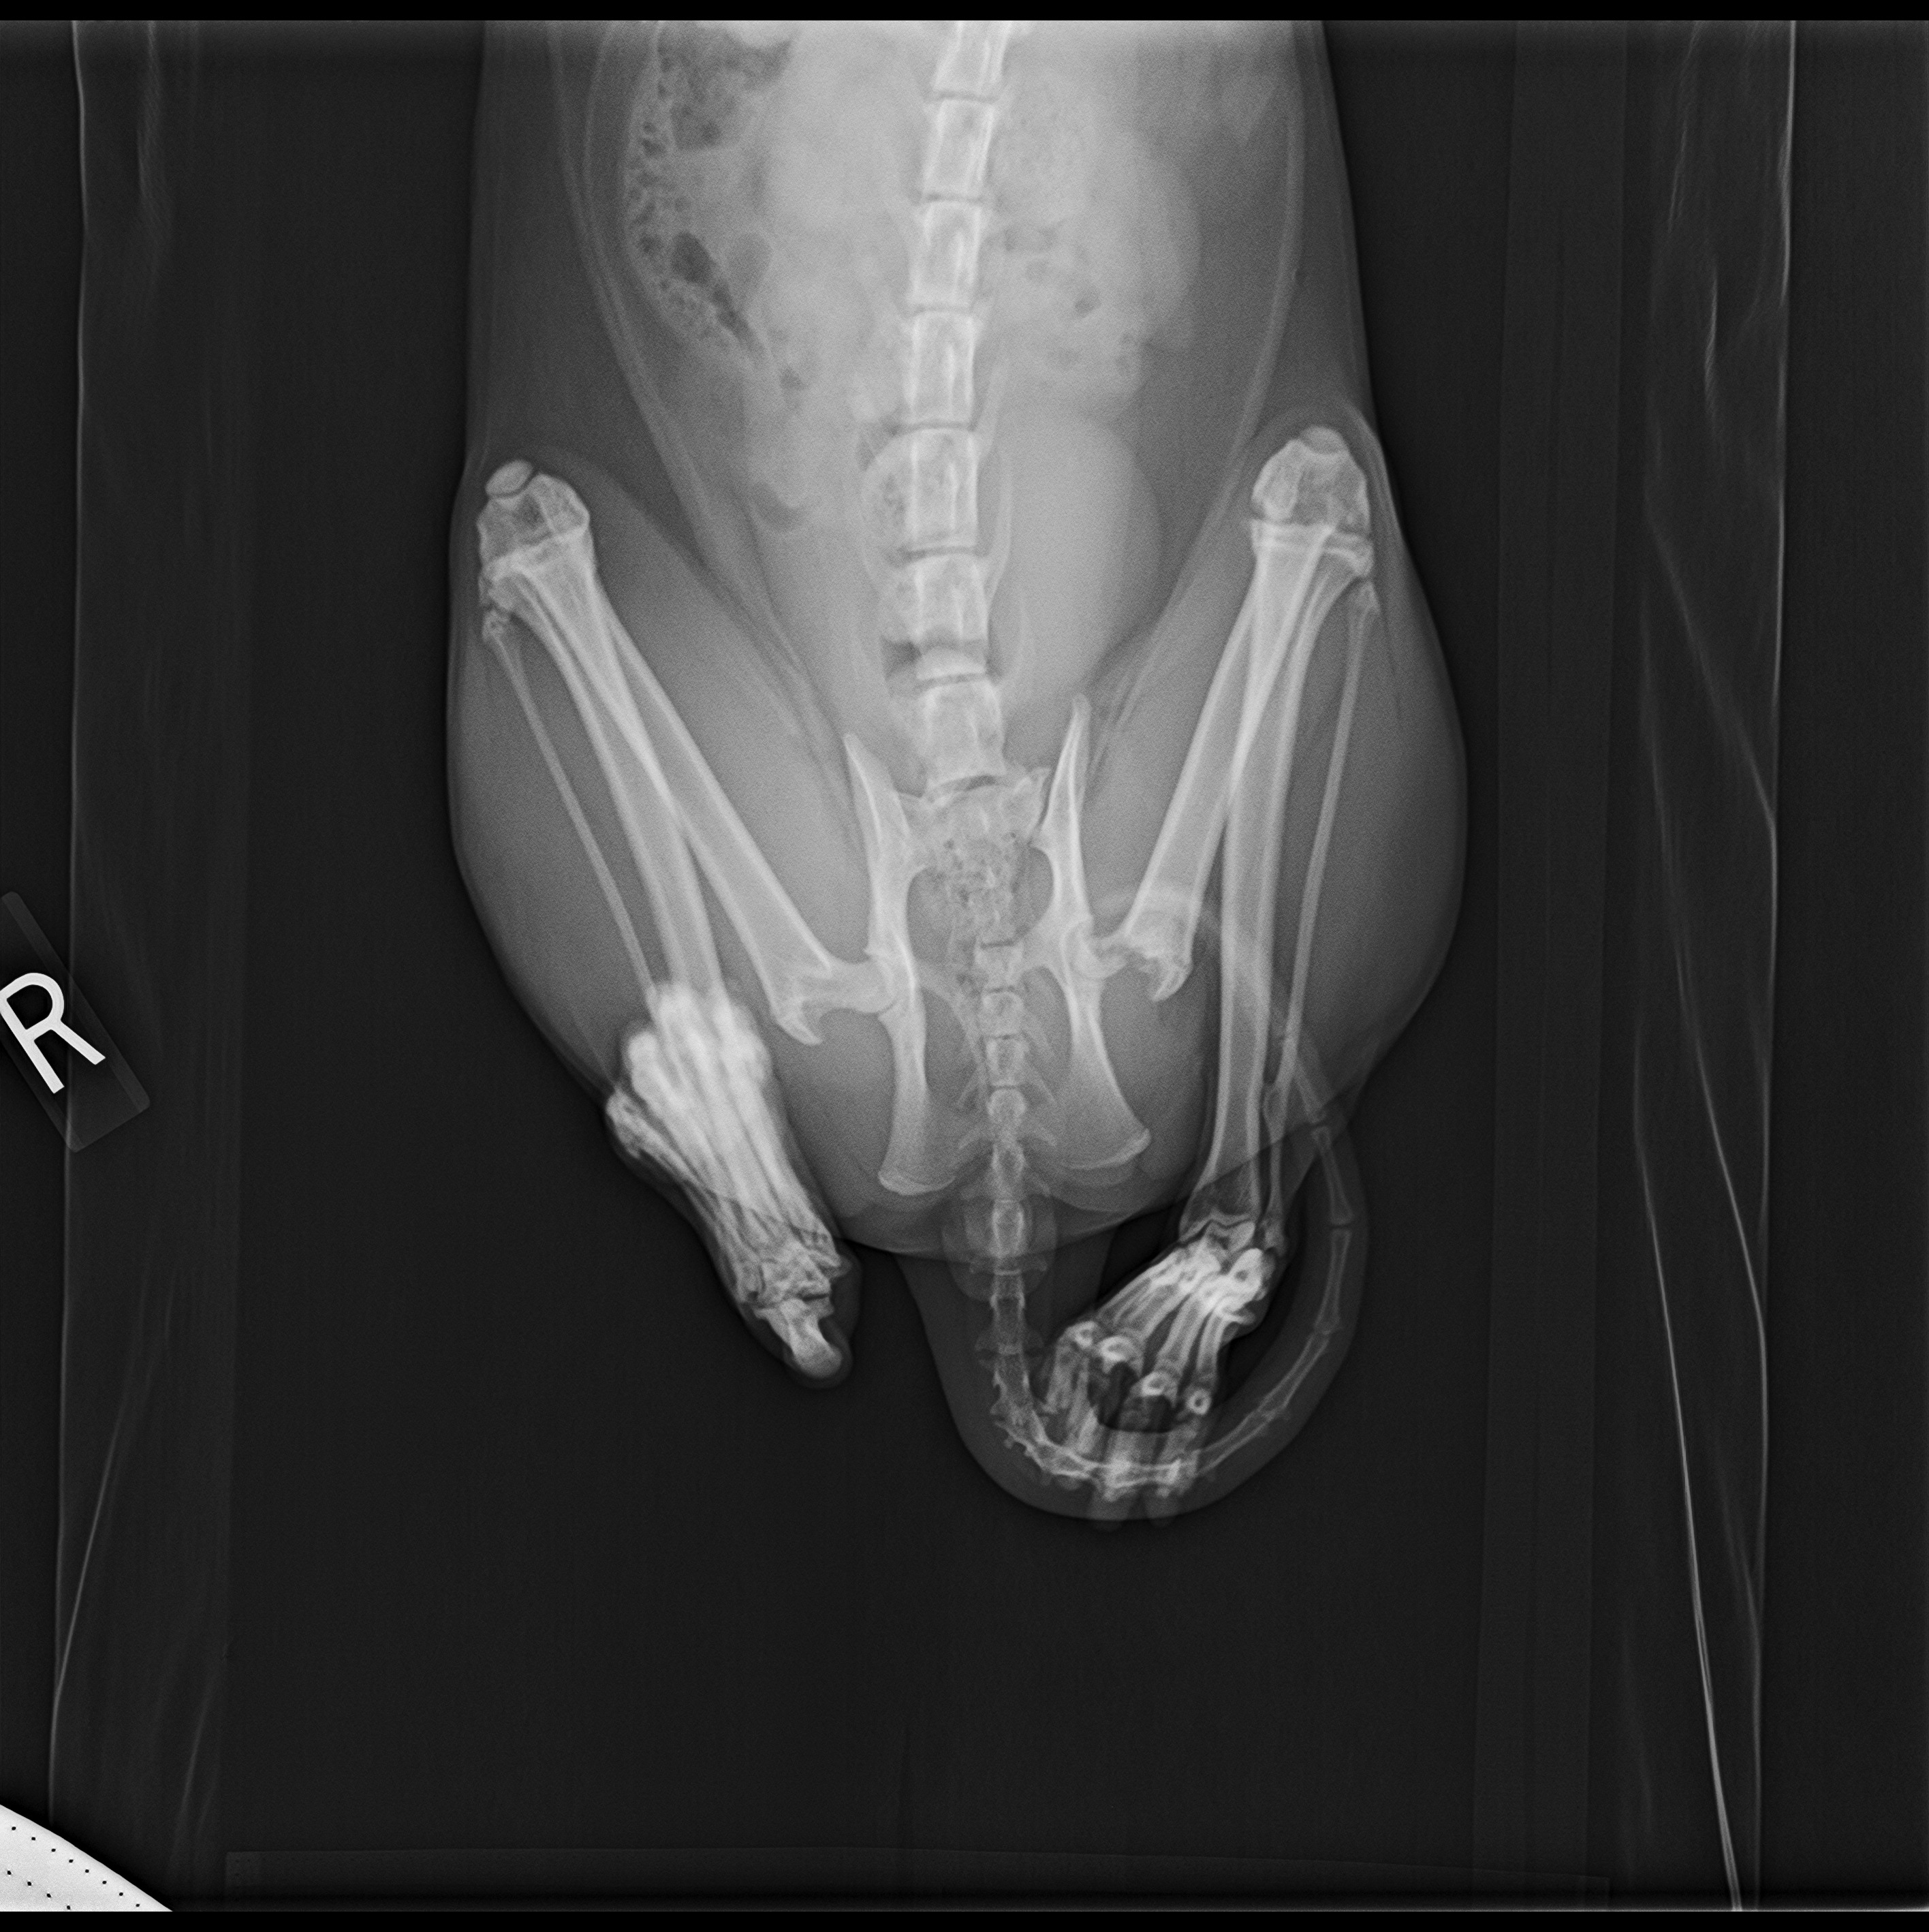

After 3-4 weeks, Mephisto was still limping in the same leg, barely putting any weight on it, and primarily balancing all his weight onto his right leg when standing and he had developed a popping in his back left hip. I decided he needed a second look and back to the vet we went. The vet felt the popping during this exam and we did xrays. Thats when we got the new diagnosis. Mephisto is experiencing Femoral Head Necrosis. Basically the ball end of his femur, where it goes into the hip socket is dead due to lack of blood flow and it had fractured. This is most likely due to the injury from his knee causing him to use the leg less. To fix this, my vet suggested a Femoral Head Osteotomy. Basically they will remove the top of his femur, clean up whatever dead tissue is there from the Necrosis, and then sew his muscle back together. The muscle will keep his leg in place while his body forms a false soft tissue joint to replace the one that has been taken out. From all the research ive done, this is a fairly common procedure for young cats but will be quite the healing process for him.